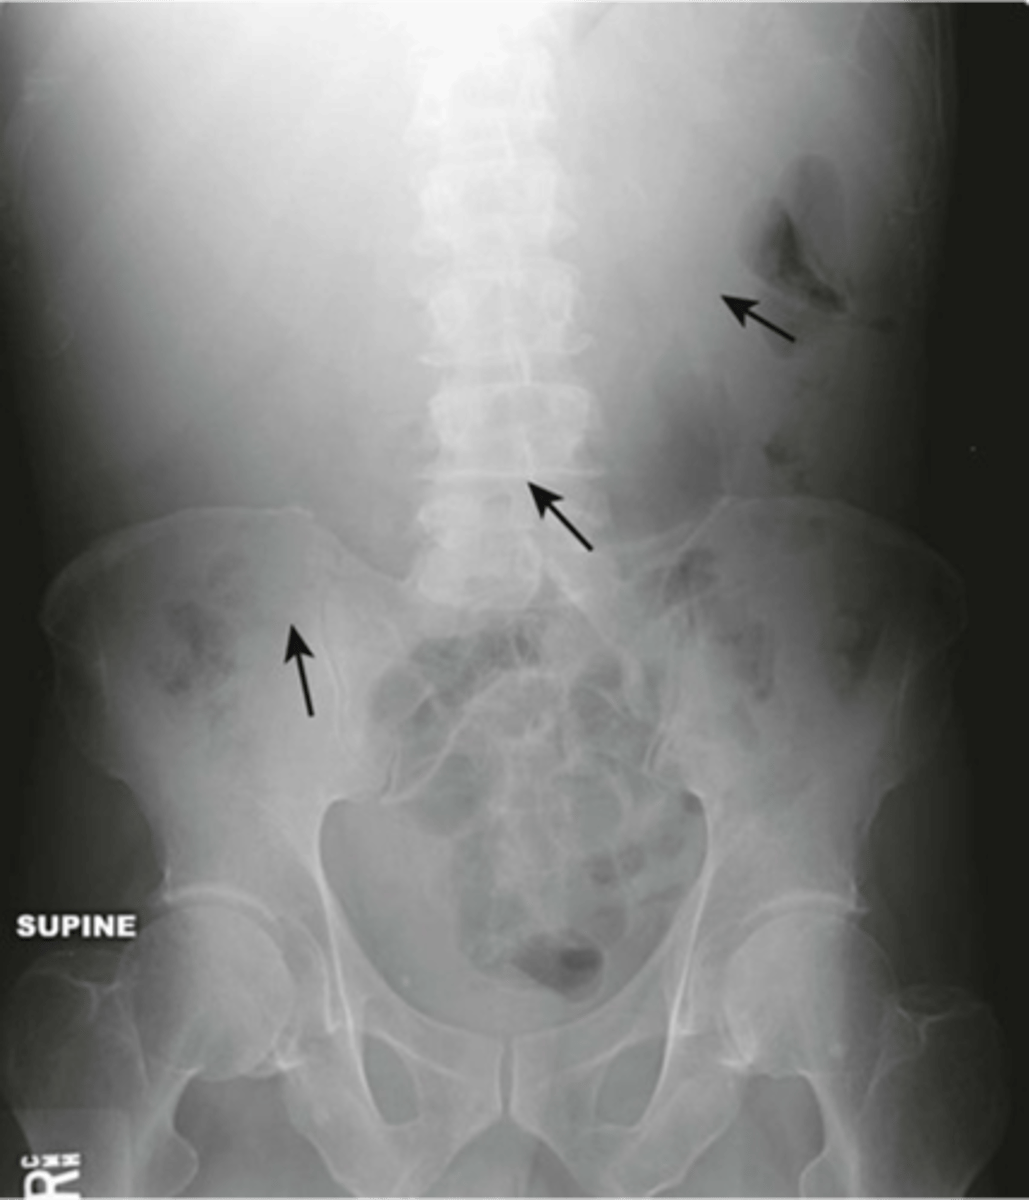

Abnormal organs on AXR

Hepatomegaly